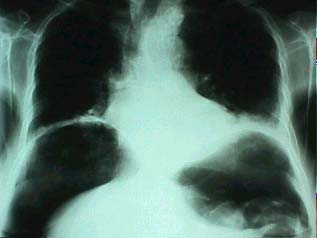

Laboratorio: leucocitos: 13.600. Segmentados 86 % , linfocitos: 4%. Se realizó estudios: (fig 1);

Rx tóraco abdominal: en la que se identifica importante cantidad de aire en los espacios subfrénicos bilaterales y que están en relación a perforación de víscera hueca.